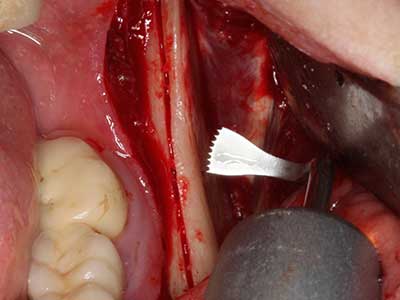

Quando le procedure chirurgiche vengono eseguite sull'osso nelle immediate vicinanze di strutture sensibili, come vasi sanguigni o nervi, gli strumenti rotanti pongono un rischio significativo di lesione iatrogena. I dispositivi piezoelettrici possono essere utili per la preparazione delle coperture ossee e la rimozione del tessuto duro in prossimità dei nervi, in particolare per la loro esposizione dopo una lesione iatrogena, ma anche durante la lateralizzazione dei nervi per le procedure di resezione e ricostruzione o il posizionamento di impianti (figg. 17-20). Il contatto leggero tra puntina piezoelettrica e nervo non causa generalmente danni, ma se si procede senza prestare attenzione con movimenti a sega o raccordi con residui di substrati ossei possono verificarsi danni al nervo temporanei o anche permanenti. Il rischio di danno, tuttavia, è considerato sostanzialmente inferiore al rischio presente utilizzando seghe o frese (Pereira, Gealh et al. 2014).

Fig. 18: preparazione di una copertura corticale con sega piezoelettrica per osso (Piezomed, W&H).

Fig. 19: sito chirurgico dopo neurolisi e rimozione dell'osteoma.

Fig. 20: la copertura ossea rimossa viene riadattata e fissata con una vite per osteosintesi (KLS Martin, Tuttlingen).